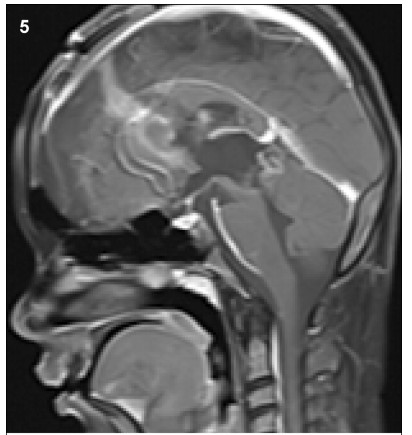

1 Case presentation 1.1 History A space-occupied cystic lesion in the rear of the third ventricle was detected in an 8-year-old boy presenting with symptoms of raised intracranial pressure (ICP) and a diagnosis of “cystic lesion” 3 years ago (Figure 1). He underwent a ventricle-peritoneal shunt operation without serum tumor marker test and became asymptomatic soon after the operation. Intermittent regular brain Magnetic Resonance Imaging (MRI) demonstrated no evidence of massive aggrandizement during the following 2 years. Then, 2 months ago,he rapidly developed unsteady gait and confined ocular motor function,followed by acute aggravating clinical symptoms. MRI scans showed that the mass had remarkably enlarged in size and the solid component had become predominant,instead of the prior cystic lesion. Furthermore,the transitional parenchyma tumor was heterogeneously and notably enhanced in contrast-enhanced MR image (Figure 2).

Figure 1 The MRI (2013) showed a cystic lesion in the rear of third ventricle.

Figure 2 The MRI (2015) showed the mass remarkably enlarged in size and the solid component became predominant instead of prior cystic lesion.